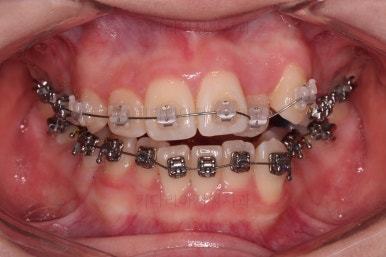

장치를 처음 부착한 사진입니다.

이번 환자분은 특징적으로 윗니의 장치와 아랫니의 장치가 다르죠.

윗니는 좀 더 심미적인 세라믹으로 선택하셨고 아랫니는 비교적 저렴하고 부피가 약간 작고 튼튼한 메탈로 진행했습니다.

그래도 됩니다.

심지어는 같은 회사 제품이 아니더라도 적절하게 세팅을 고려하면 섞어 사용하는 것도 가능하답니다.